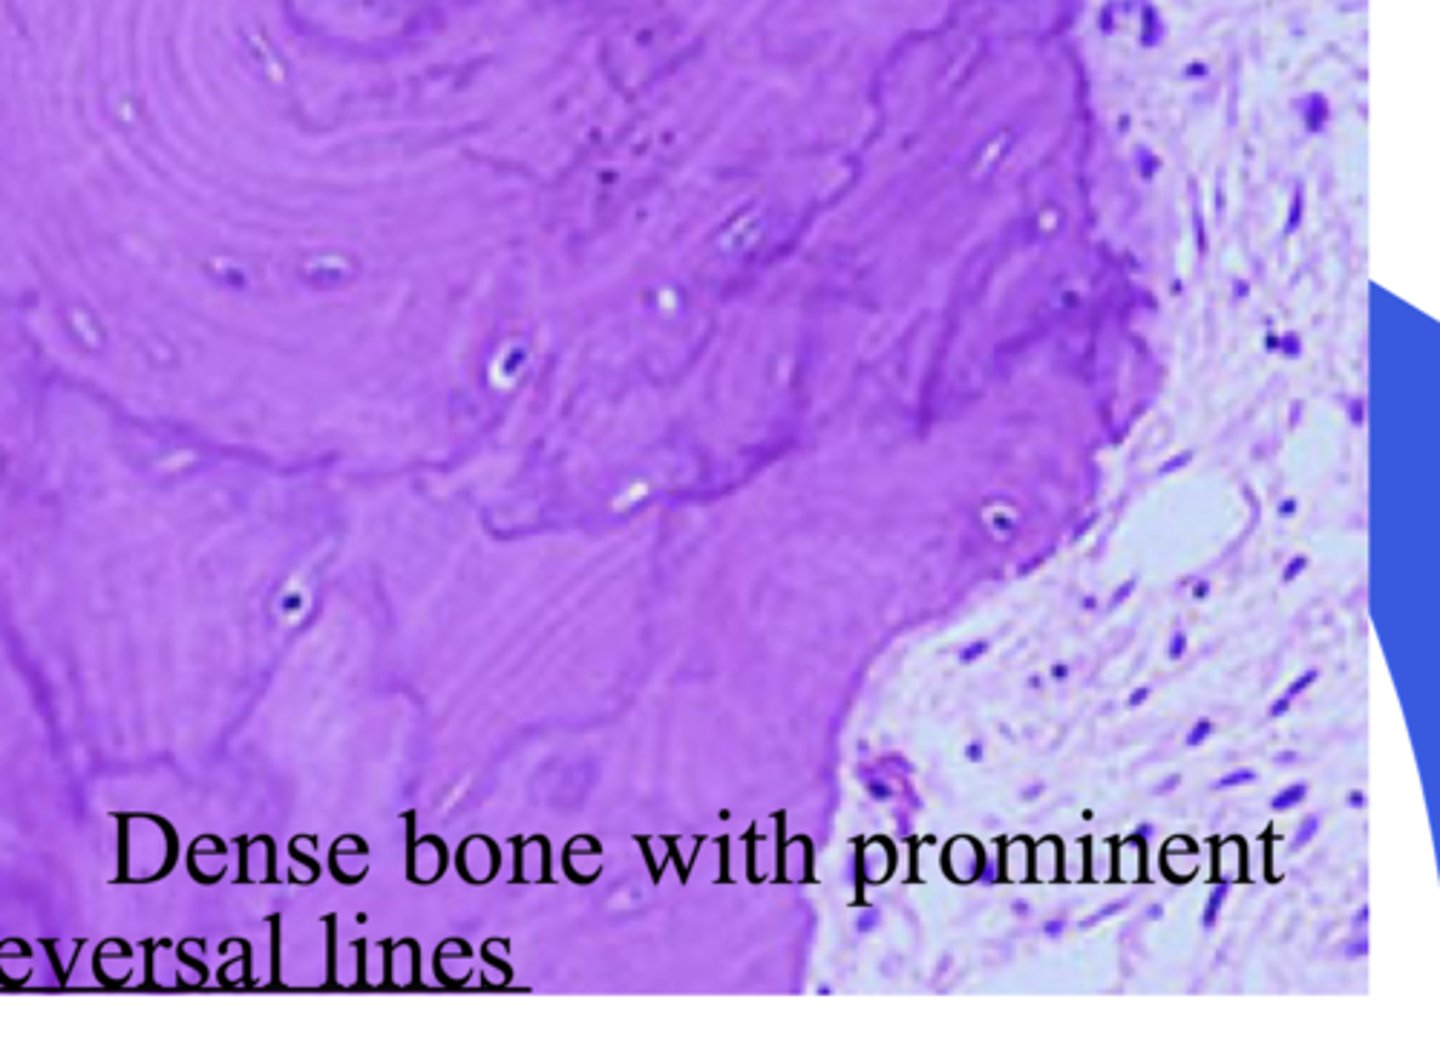

Paget's disease - histology

- Reversal lines